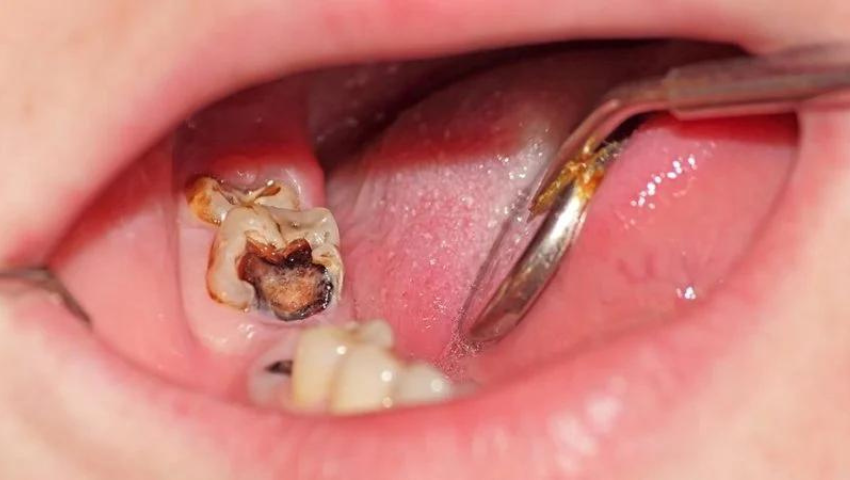

Viêm tủy răng số 7 xảy ra khi chiếc răng số 7 bị sâu, phần tủy lộ ra ngoài do răng bị vỡ, bể. Lúc này, vi khuẩn sẽ xâm nhập vào bên trong và gây viêm nhiễm, đau nhức, ảnh hưởng xấu đến sức khỏe răng miệng của người bệnh.

- Sâu răng: Răng số 7 có vị trí nằm sâu ở bên trong hàm nên dễ khiến cho các mảnh vụn thức ăn thừa còn sót lại bám vào quanh răng, khó vệ sinh bằng các công vụ vệ sinh hàng ngày. Điều này đã tạo điều kiện cho vi khuẩn sâu răng phát triển, tấn công và phá hủy răng từ ngoài và trong, từ men răng đến ngà răng, sau đó ăn vào buồng tủy ở thân răng từ đó dẫn đến viêm tủy răng.

- Răng bị sứt mẻ, vỡ: Khi gặp tổn thương, răng sẽ bị vỡ hay bị sứt mẻ, từ đó sẽ khiến cho buồng tủy bị lộ ra ngoài, làm cho vi khuẩn dễ dàng xâm nhập vào tủy gây viêm nhiễm cho răng.